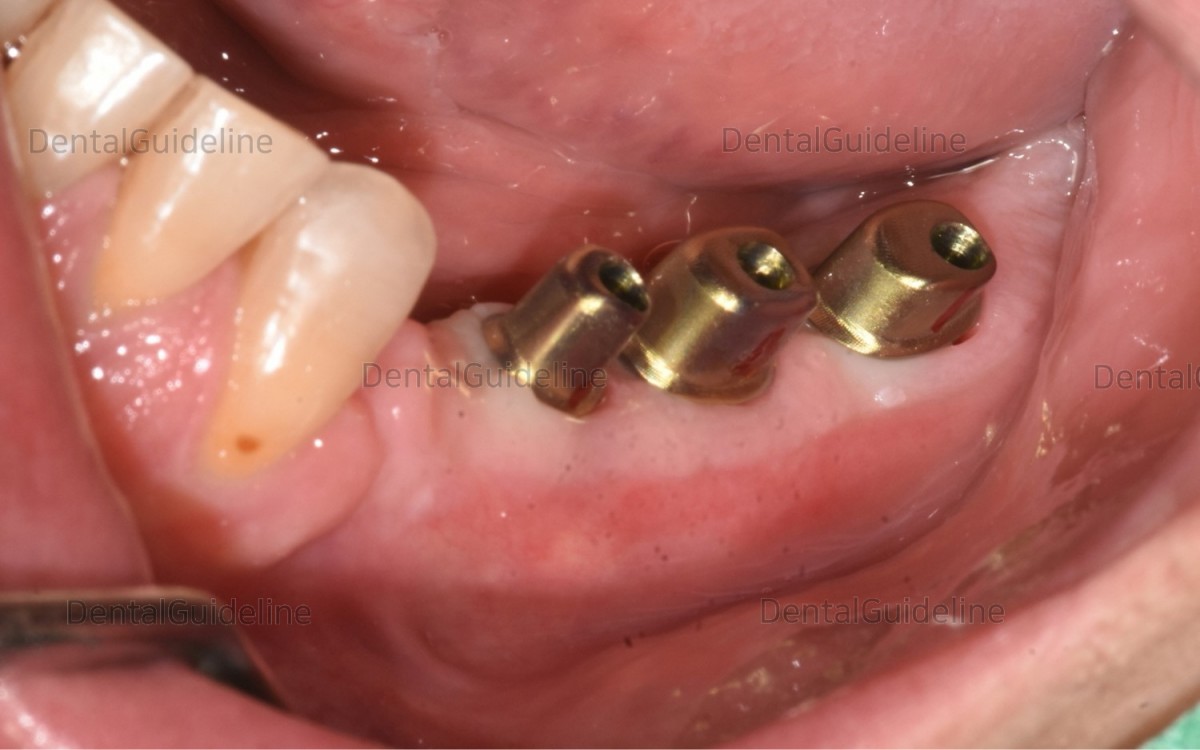

Intraoral

view shows the healing status of post-op 7 weeks.![]()